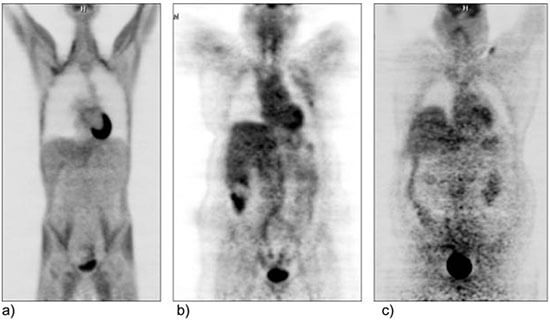

An additional consideration for molecular imaging studies is the dose of radioisotope that can safely be administered. Radioisotope dosing is weight-based and therefore increased doses are required in patients with increased weight to allow for diagnostic imaging. However, there are upper limits to the dose that can be safely administered. A dose reduction required for safety reasons will result in a decreased signal-to-noise ratio and decreased image contrast, ultimately decreasing the imaging quality. In addition, patients with obesity often require longer molecular imaging scan times, which can lead to motion artifact, which may further decrease image quality.

Coronal PET images from three patients of varying diameters and weights (patient weight increases from a to c) demonstrating increased image degradation as patient’s diameter/weight increases.2